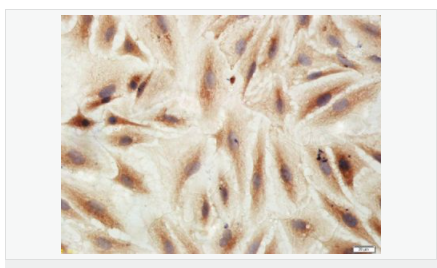

| 產(chǎn)品應用 | WB=1:500-2000 IHC-P=1:100-500 IHC-F=1:100-500 Flow-Cyt=3ug/test ICC=1:100-500 IF=1:100-500 (石蠟切片需做抗原修復) not yet tested in other applications. optimal dilutions/concentrations should be determined by the end user. |

| 產(chǎn)品介紹 | This gene encodes an adenosine receptor that is a member of the G protein-coupled receptor superfamily. This integral membrane protein stimulates adenylate cyclase activity in the presence of adenosine. This protein also interacts with netrin-1, which is involved in axon elongation. The gene is located near the Smith-Magenis syndrome region on chromosome 17. [provided by RefSeq, Jul 2008]. Function: Receptor for adenosine. The activity of this receptor is mediated by G proteins which activate adenylyl cyclase. Subcellular Location: Cell membrane; Multi-pass membrane protein. Similarity: Belongs to the G-protein coupled receptor 1 family. SWISS: P29275 Gene ID: 136 Database links: Entrez Gene: 136 Human Omim: 600446 Human SwissProt: P29275 Human Unigene: 167046 Human Important Note: This product as supplied is intended for research use only, not for use in human, therapeutic or diagnostic applications. |